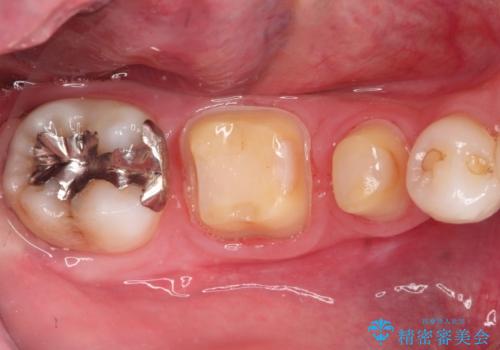

- 虫歯の治療を主訴に来院されました。

奥歯は不可逆性歯髄炎の診断のもと、根管治療を行なった後、被せ物の治療を行なっております。

根管治療を行なった歯は被せ物を使用することで、破折しづらくなります。